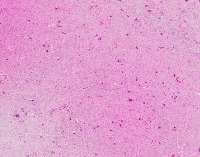

Medical Diagnostics: geckler5 can be used in healthcare facilities to analyze images of tissue samples, blood smear slides, or other medical images to detect the presence and distribution of White Blood Cells (WBC) and Erythrocyte Hemoglobin Concentration (EHC). This can aid in diagnosing diseases such as infections, anemia, or leukemia.

Research and Development: Scientists working in the field of hematology or immunology can use geckler5 to analyze large datasets of blood samples in their research studies. This can help them better understand blood cell morphology, variations, and concentrations in different conditions, ultimately leading to new medical discoveries.

Pharmaceutical Testing: The pharmaceutical industry can utilize geckler5 to analyze the effects of new drugs or treatment methods on WBC and EHC levels. This would allow researchers to monitor the efficacy, side effects, and other critical factors for drug trials and approval processes.

Educational Purposes: Educational institutions teaching medical or biological courses can implement geckler5 as a learning tool, helping students to identify and differentiate between various blood components. This can enhance their understanding of blood cell compositions and related medical conditions.

Blood Donation Centers and Blood Banks: geckler5 can be employed to assess the quality of blood donations in terms of WBC and EHC levels. This automated analysis would help staff ensure that donated blood meets necessary standards and is safe for transfusion into patients.